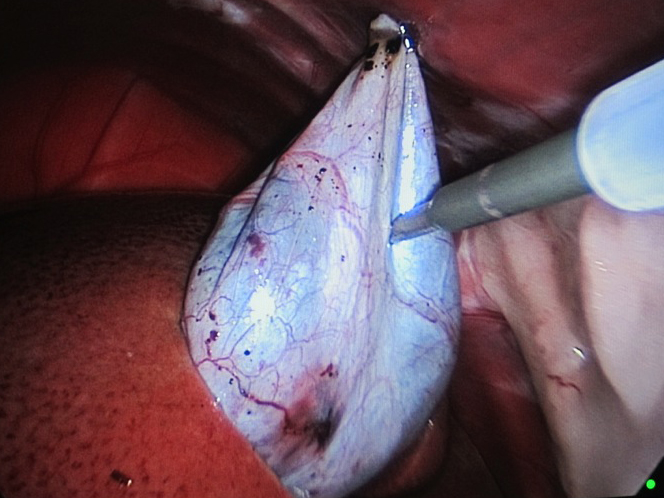

体の外に出すためお腹の中で袋に入れていきます。

回収袋にいれて体外に摘出していきます。